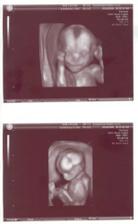

♥♥ 26.3.2008 3D UZ - bylo to užasný - miminko sebou pořád šilo, cucalo si ručičku, ukazovalo na nás dlouhej nos a taky nám zamávalo - opravdu to stojí za to 🙂

- měříme 25 cm a vážíme 350 g♥